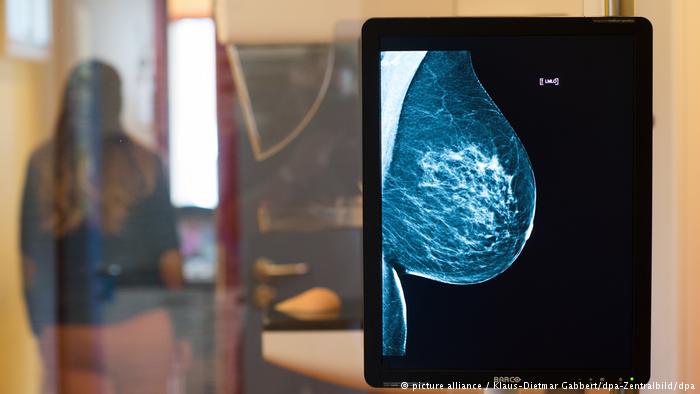

ومن بين هؤلاء فيليز دمير، التي فقدت بصرها. لكنها تستطيع أن ترى ببصيرتها ما قد يغيب عن الأطباء من تغييرات في أنسجة الثدي لدى مرضاهم، والتي يمكن أن تكون السبب وراء هذا المرض. بعد مرحلة التشخيص بالأصابع، تسجل دمير ملاحظاتها وتسلمها للطبيب لإجراء كشف بالأشعة.

في هذا الصدد، يقول البروفيسور ميشائيل لوكس من مستشفى أمراض النساء في جامعة إرلانغن: "أعتمد على الملاحظات التي تسجلها السيدة دمير عن طريق حاسة اللمس بأصابعها. بعدها أجري فحصاً بالأشعة. والنتيجة تكون أفضل مقارنة بالفحوصات التي يجريها الطبيب لوحده".